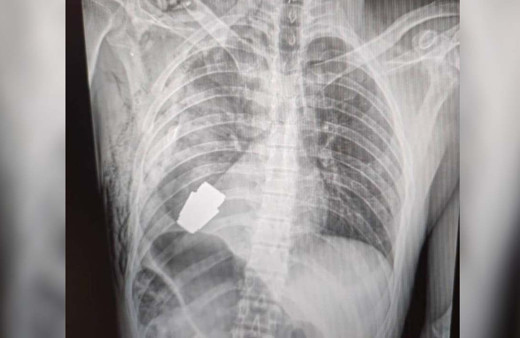

Ukrayna